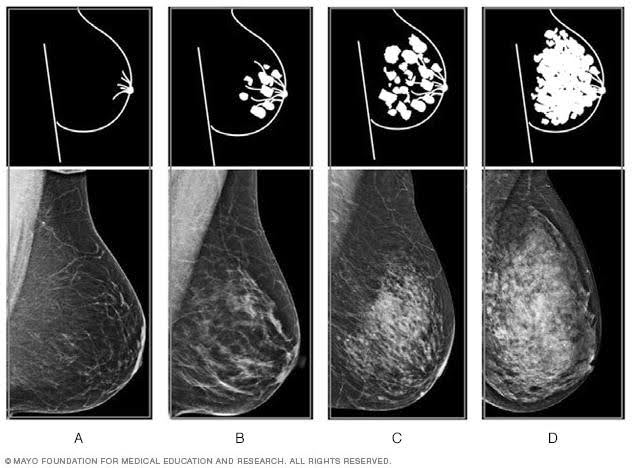

De American College of Radiology (ACR) heeft de categorieën voor borstdichtheid gedefinieerd in hun Breast Imaging Reporting and Data System (BI-RADS). Ze verdelen de dichtheid van borstweefsel in vier categorieën, die vaak door radiologen worden gebruikt bij het beoordelen van mammogrammen:

ACR Categorie A – Volledig vetweefsel: De borsten zijn bijna volledig samengesteld uit vetweefsel. Dit betekent dat afwijkingen op de mammografie meestal goed zichtbaar zijn.

ACR Categorie B – Enkele verspreide gebieden van dicht weefsel: Er zijn enkele gebieden met dicht klierweefsel, maar het grootste deel van de borsten is vetweefsel. Afwijkingen zijn over het algemeen nog steeds goed zichtbaar.

ACR Categorie C – Heterogeen dicht weefsel: Een groot deel van de borst bestaat uit dicht weefsel tussen de 50-75%, wat het moeilijker maakt om afwijkingen te detecteren. Tumoren of andere problemen kunnen worden gemaskeerd door het dichte weefsel.

ACR Categorie D – Extreem dicht weefsel: Bijna de gehele borst bestaat uit dicht klierweefsel, voor meer dan 75%. Dit is de categorie waarin afwijkingen het moeilijkst te detecteren zijn met alleen een mammografie, waardoor aanvullende beeldvorming, zoals een MRI of echografie, vaak wordt aanbevolen.